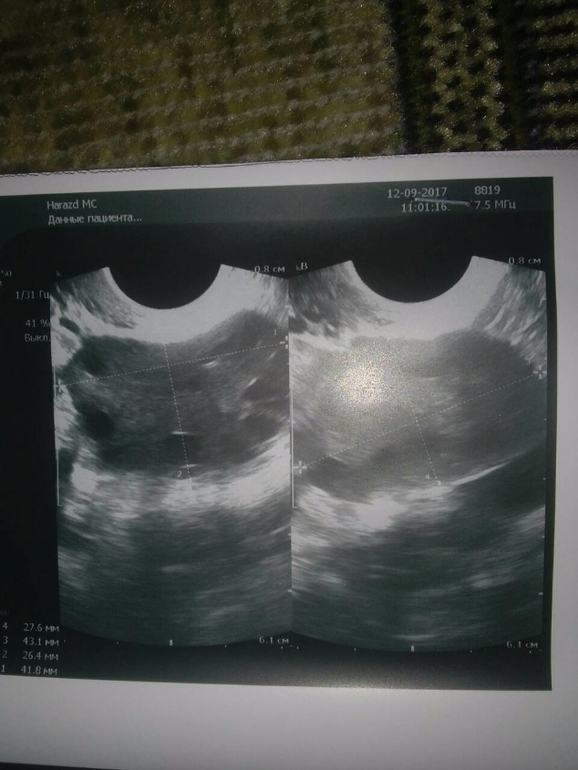

пошла на узи сегодня и вот что мне написали(фото прилагаю) умеренная гиперплазия эндометрия

умеренная гиперплазия эндометрия